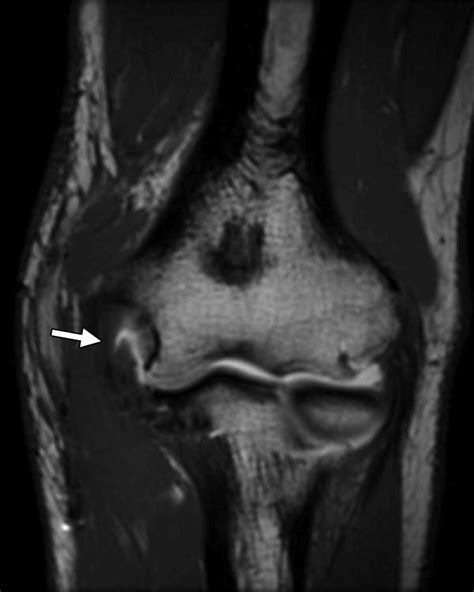

To determine if you are suffering from a ruptured ulnar collateral ligament, a medical professional will conduct a physical examination and utilize advanced imaging. The doctor will perform a "valgus stress test," where they apply gentle pressure to the outside of the elbow while the arm is slightly bent to see if there is excessive laxity or reproduction of pain.

MRI (Magnetic Resonance Imaging) Visualizing the tear and evaluating the severity of the rupture.